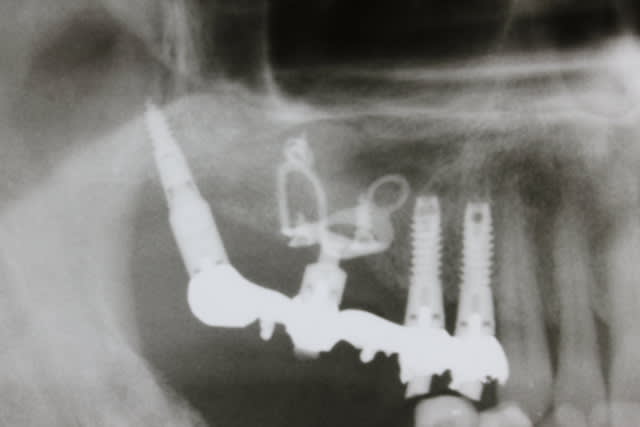

Patient d un pote chez qui on a pris l option décrite

1. poser les 4 cylindres des Pm

2. attendre 3 mois intégration des 4 cylindres

3. poser les plaques et les deux petits ptérygos avec MCI/MCD

Je vous rassure on a depuis posé en bas 6 cylindres pour remplacer les 6 et 7